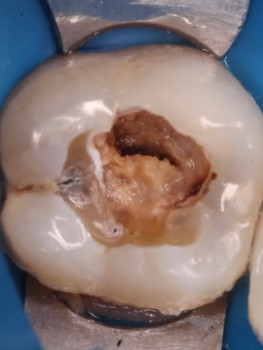

1 работа в портфолио